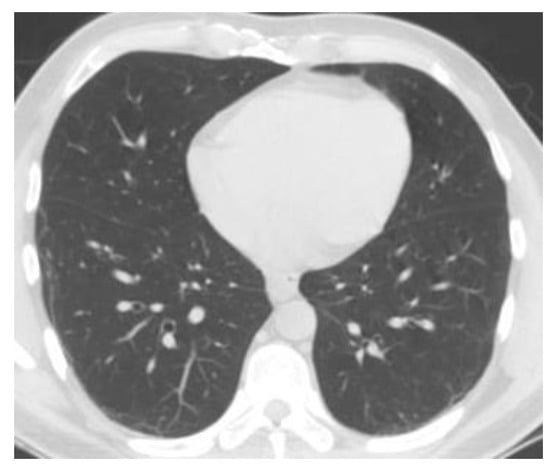

Figure 9 and Figure 10 show the original CT lung image, respectively, and the defined mask for the COVID-19 lung CT image, framed in a blue border in Figure 10.

Figure 10 presents the applied mask across the COVID-19 lung CT image, framed in a blue colour border.